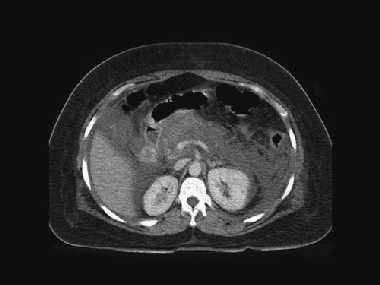

Figura 7: Imagen TC necrosis pancreática.

Colección única mal definida Balthazar grado D. Necrosis

pancreática mayor al 50%. Indice de severidad alto (9 puntos).